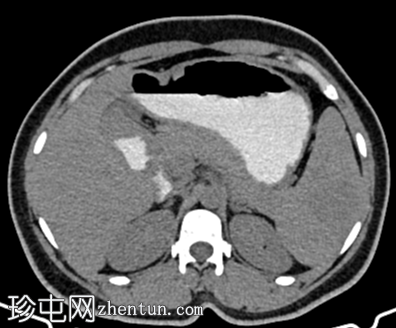

矢状位增强扫描

动脉期

脾脏内可见一圆形低密度病灶,动脉期呈周边环状强化,延迟期呈轻微向心性充盈

未见钙化、动静脉畸形或动脉瘤

学特征为:病灶周围呈放射状强化,中心呈放射状强化,周围环状强化,中心充盈轻微。增强扫描后可见中央星状瘢痕。